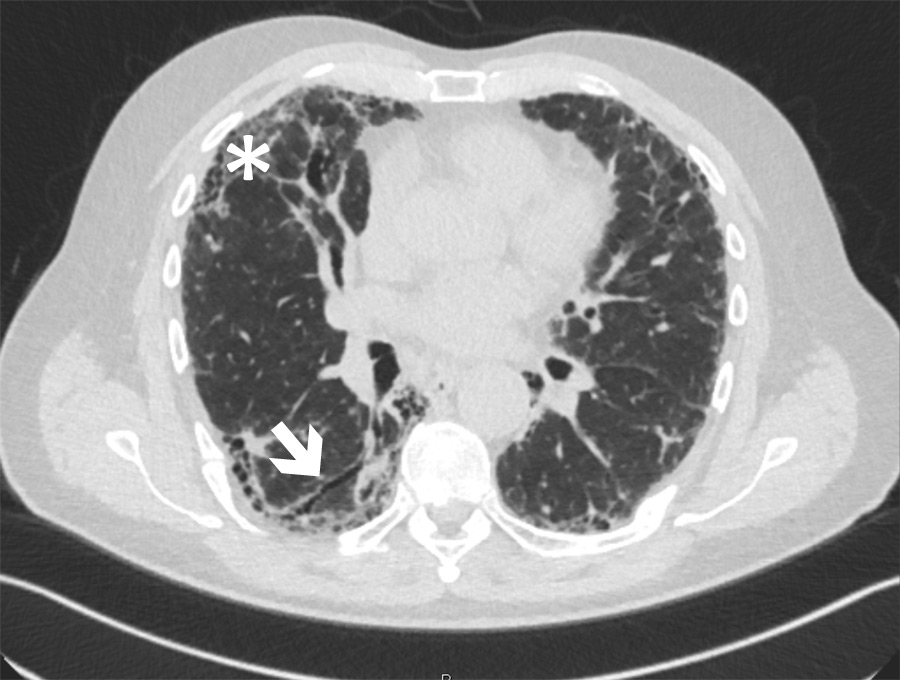

Figure 1

Chest computed tomography scan of a patient with idiopathic pulmonary fibrosis. Typical radiological pattern of usual interstitial pneumonia with traction bronchiectasis (arrow) and subpleural honeycombing (star) is shown.

For diagnosis of IPF, high-resolution computed tomography (HRCT) of the lung is essential. Radiological criteria for IPF are classified into three categories: UIP pattern, possible UIP and inconsistent with UIP pattern [1]. The diagnosis of a UIP pattern requires subpleural and basal predominance, reticular abnormalities, honeycombing with or without traction bronchiectasis (example see fig. 1) and absence of features inconsistent with UIP pattern, such as upper or mid-lung predominance, peribronchovascular predominance, extensive ground glass shadowing, profuse micronodules, discrete cysts, diffuse mosaic attenuation or air trapping, and consolidation in bronchopulmonary segments or lobes [1]. In addition to HRCT, we perform bronchoscopy and BAL if possible, as lymphocytosis >15% or eosinophilia >1% favours an alternative diagnosis to IPF [48, 49]. In specific cases, transbronchial biopsies and/or cryobiopsies are taken, in particular to rule out differential diagnoses such as sarcoidosis or lymphangiosis carcinomatosa.